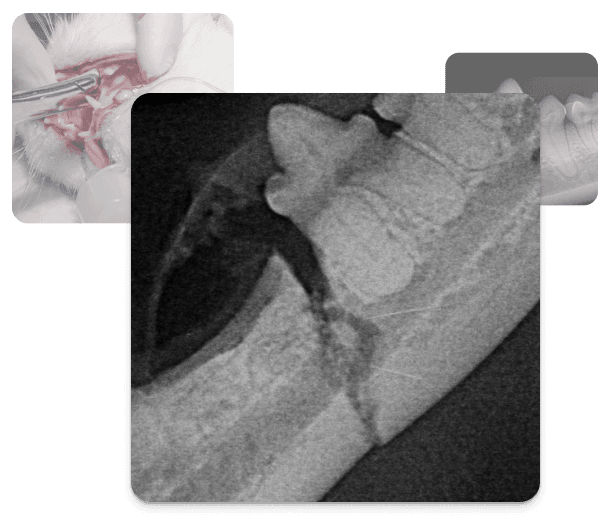

Orale Frakturen treten in chirurgisch kontaminierten Feldern auf, die Zähne enthalten und unter kontinuierlicher Kaubelastung stehen, Komplexitäten, die standard-orthopädische Verfahren unzureichend machen und spezialisierte oralchirurgische Expertise erfordern.

Mandibularkörperfrakturen werden je nach Lokalisation, Zahnbeteiligung und Knochenstatus mittels interdentaler Verdrahtung, Acrylschienen oder Miniplattenosteosynthese versorgt. Symphysenseparationen (häufig bei Katzen nach Trauma) erfordern interdentaler Stabilisierung plus vollständige orale Beurteilung zum Ausschluss begleitender Pathologien.

Pathologische Frakturen bei geriatrischen Kleinhunden durch parodontalen Knochenverlust erfordern gute präoperative Planung, da kompromittierter Knochen selten eine Routinefixation ermöglicht.